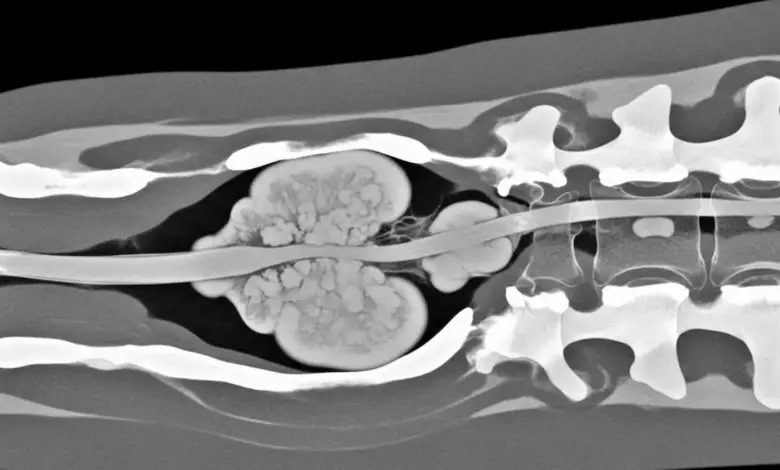

- Ressonância magnética: melhor para medula, nervos e partes moles.

- Tomografia: detalha o osso e ajuda a planejar cirurgia e biópsia.

A confirmação do tipo de tumor costuma exigir biópsia. Ela define o subtipo, o grau de agressividade e quais tratamentos respondem melhor, orientando assim a conduta.